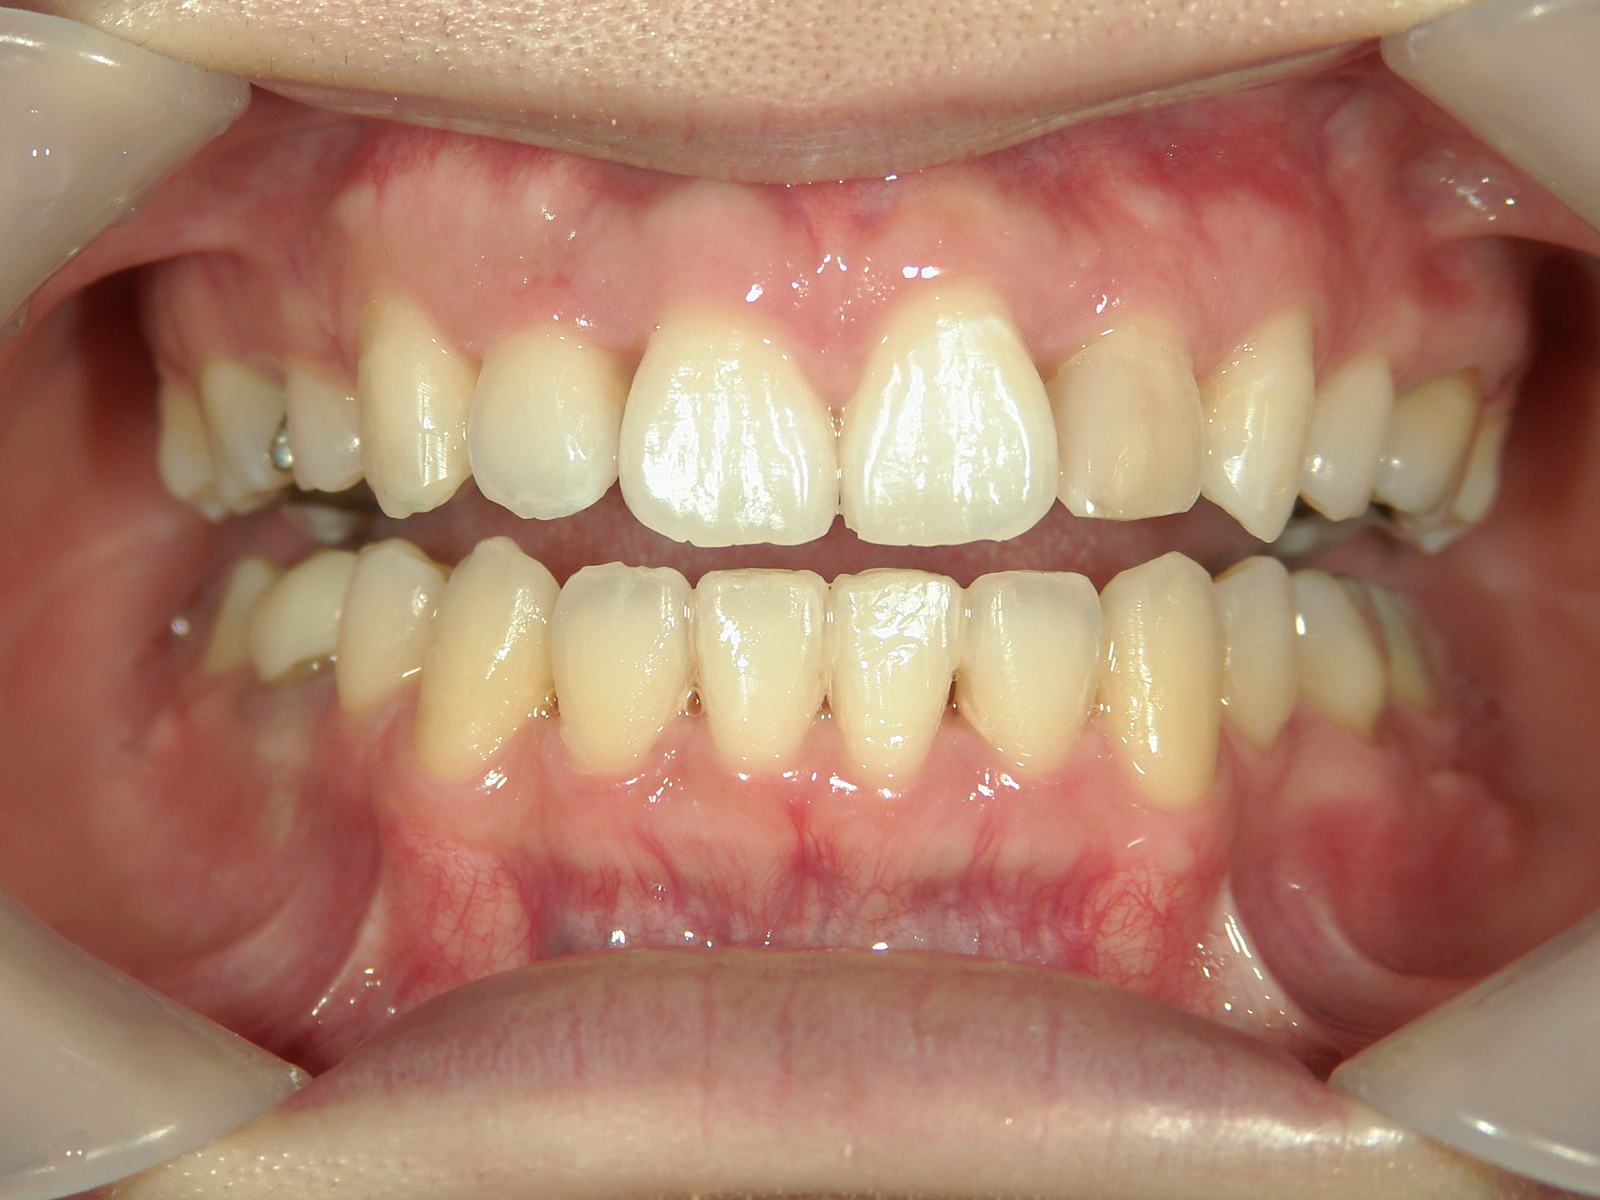

舌側ワイヤー矯正 症例(25)

左右上 第一小臼歯(2本)、左右下 第二小臼歯(2本)を抜歯。

| 治療期間 | 3年(矯正装置(BH・QH)併用期間も含む) |